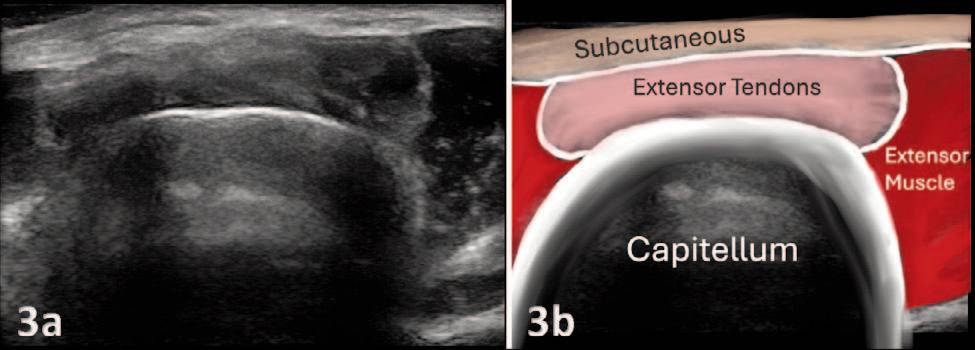

135 Diagnostic Musculoskeletal Ultrasound for the Evaluation of the Lateral Elbow: Implications for Rehabilitation Providers.

Manske RC, Wolfe C, Page P, Voight M.